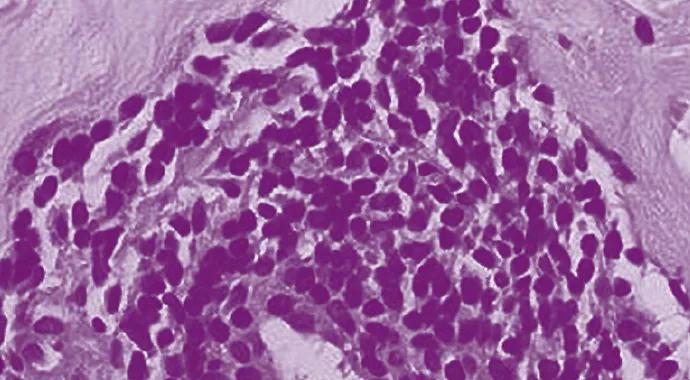

The interest in investigating abatacept in GCA and TAK was based not only on this unmet need to identify treatment options beyond prednisone but also on the safety profile of this medication and its mechanism of action. Abatacept is comprised of the ligand binding domain of CTLA4 plus a modified Fc domain derived from IgG1. As CTLA4 acts as a negative regulator of CD28-mediated T cell costimulation, abatacept inhibits T cell activation. Laboratory evidence suggests that GCA and TAK are antigen-driven diseases, in which T lymphocytes play an important role. By interfering with the T cell activation, abatacept carried the potential to impact a mechanism involved in disease pathogenesis.